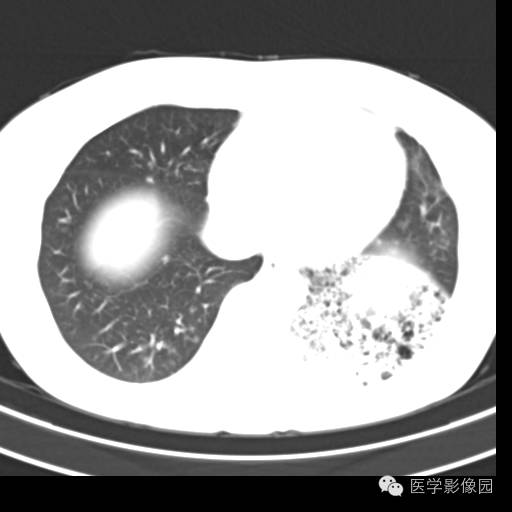

肺叶实变性支气管肺泡癌1例CT影像表现